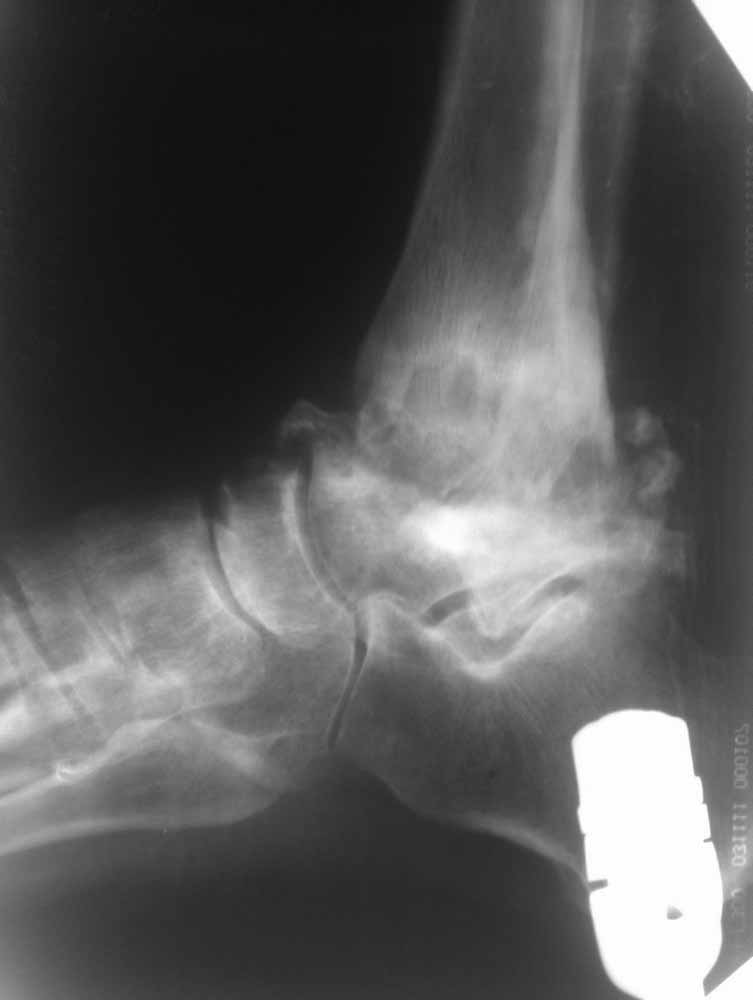

Опять прошу прощения за качество фото, но принципиальные моменты мне кажется, что видны.

Из того, что я вместе с лучевыми диагностами разглядел - нельзя исключить остеомиелит (?) - есть краевая реакция, куча элементов, похожих на секвестры. Смущает полное отсутствие местной и системной реакции - к анализам не придраться.

Про оперативное - думаем об артродезе правого голеностопа (пока и там ничего не съехало - боль в правом голеностопе усилилась из-за увеличения нагрузки), а слева (где как раз и есть некроз тарана и пилона) - открыть, чистить, бусы с антибиотиком, максимально коррекция сразу + аппарат.

Про опухоли - склоняюсь к мысли, что все таки может быть какое-то из последствий лучевой болезни (31 явка на ЧАЭС) (?!)...